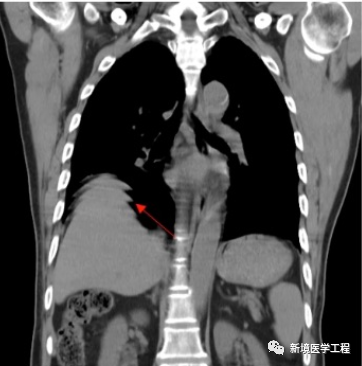

2.5「腹部放射条状伪影」

【产生原因】

在FOV以外有对比度不连续的物体。如腹部时,患者手臂放置于体侧,未上举。(部分溶剂效应)

【解决办法】

-

清除患者旁边的异物

-

勾选自适应滤波功能